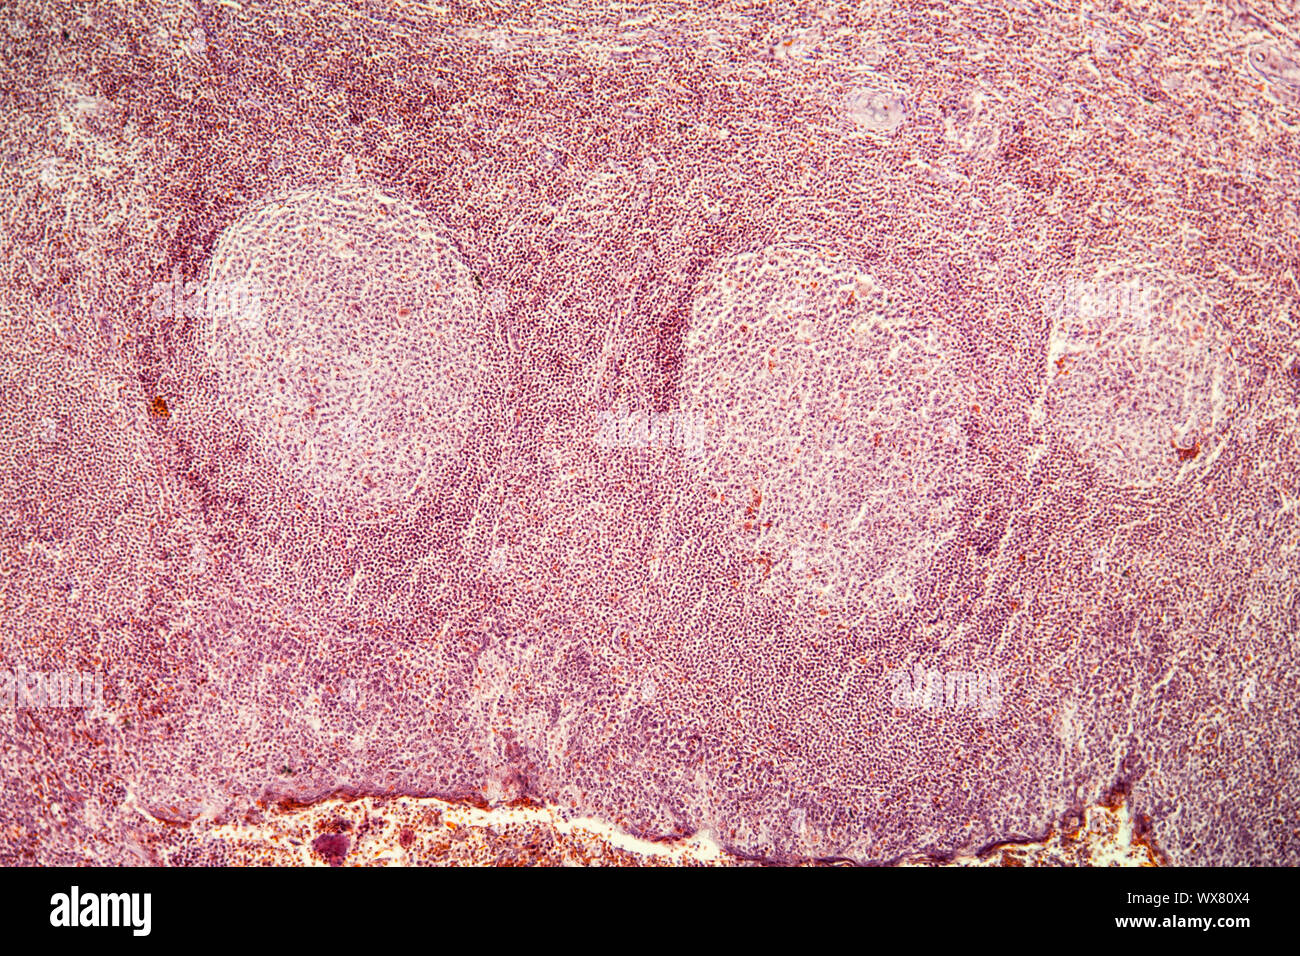

Mandelentzündung krankes Gewebe unter dem Mikroskop 100x Stockfotohttps://www.alamy.de/image-license-details/?v=1https://www.alamy.de/mandelentzundung-krankes-gewebe-unter-dem-mikroskop-100x-image274312924.html

Mandelentzündung krankes Gewebe unter dem Mikroskop 100x Stockfotohttps://www.alamy.de/image-license-details/?v=1https://www.alamy.de/mandelentzundung-krankes-gewebe-unter-dem-mikroskop-100x-image274312924.htmlRMWX80X4–Mandelentzündung krankes Gewebe unter dem Mikroskop 100x